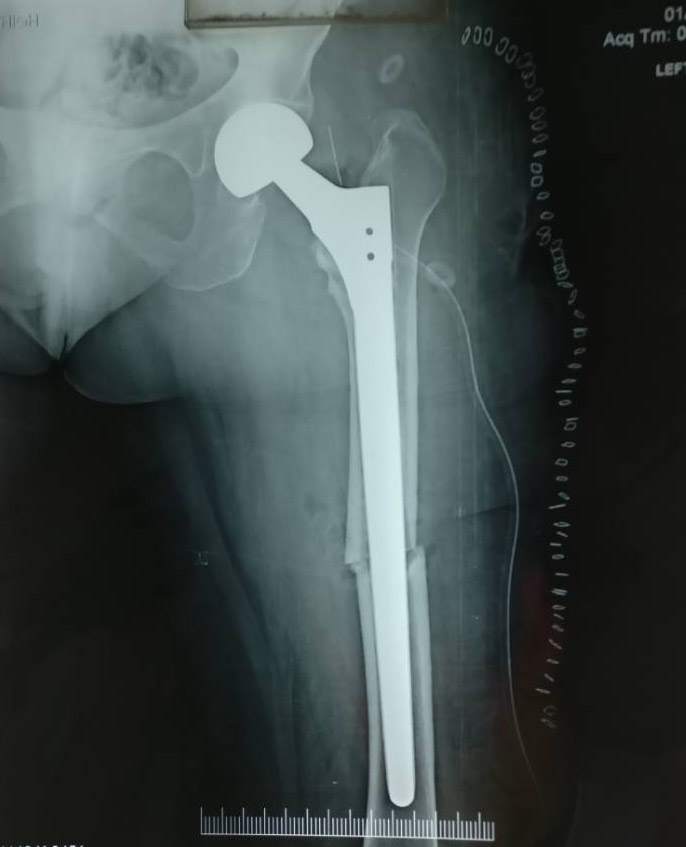

A 75 years old female from Neemuch presented to us following a fall and broken femur. She had already undergone a partial hip replacement there about 3 years back.

She underwent a successful revision partial hip replacement surgery and could walk from the very next day. The procedure was done by Dr Sachin Chhabra, Indore.